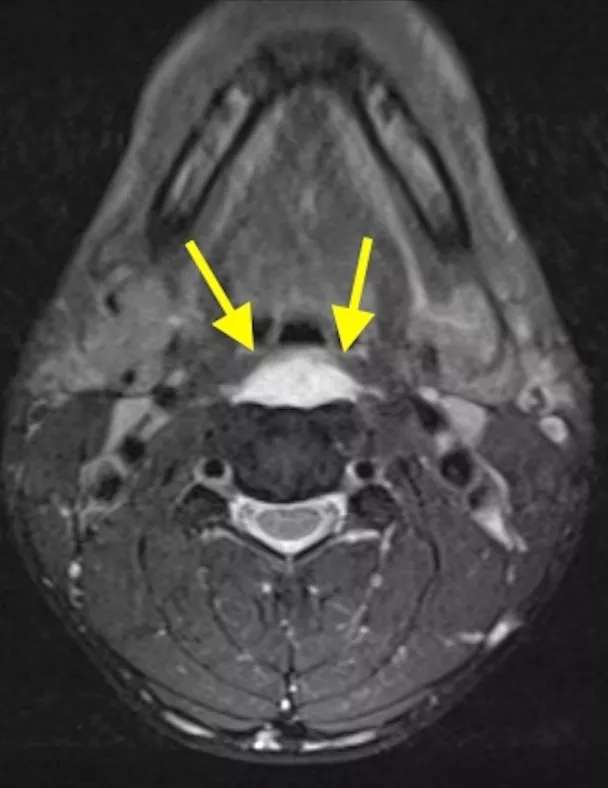

椎前积液

椎前积液和C1椎体前弓下方不规则钙化沉着

CT的高分辨率能够明确肌腱内的钙化,能够明确是钙化而不是其他骨骼来源的高密度影。钙化一般位于寰椎前弓的下方和枢椎齿状突的前方,少部分可位于下颈椎前侧。CT有助于明确椎体前积液的存在和排除其他病理表现,如骨折或脓肿。MRI对诊断不是必须,但有时可帮助确定软组织异常,排除咽后脓肿,脊椎炎或肿瘤。MRI检查T2加权在椎前可见局限性的裂隙样区域,大多位于C1-4水平,呈高信号改变,这反应是由于炎症引起的积液。T2加权、脂肪抑制序列和T1加权对鉴别积液和脂肪组织、含脂肪的骨髓以及咽后感染、脊椎炎有重要作用。MRI检查在钙化检查方面存在不足,T2加权呈低信号。